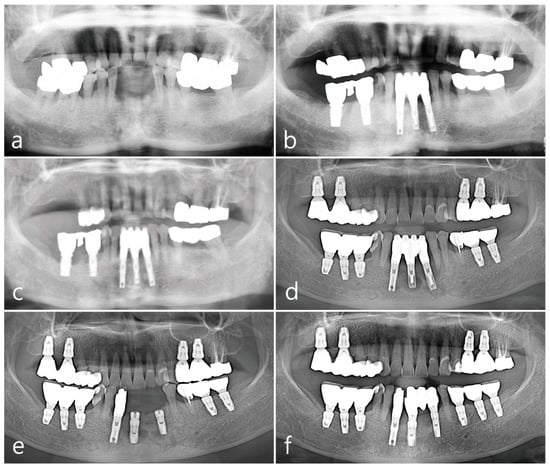

2. Case Presentation

2.1. Mandibular Right Posterior Region

2.2. Maxillary Left Posterior Region

2.3. Mandibular Left Posterior Region